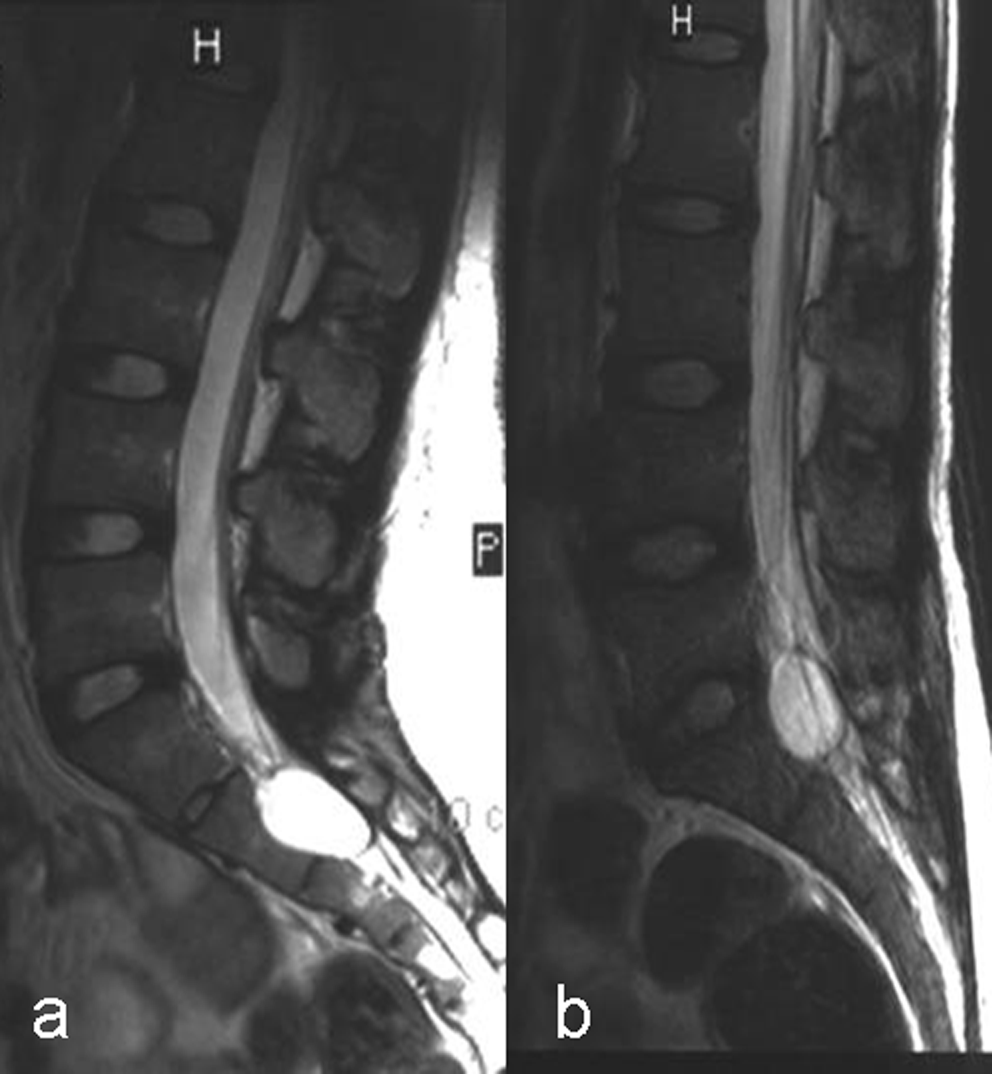

Results: All cystic lesions showed hypointense signal intensity on T1WI and hyperintense signal intensity on T2WI, but the nerve root showed iso-intensity on T1WI and low signal intensity on T2WI. They were linear in shape on sagittal view, and hypo intense dotted spots within the cysts on traverse view. Surrounding structures of the larger cysts were compressed and had bone erosions in some cases; the spinal canal and the intervertebral foramen on the affected side were enlarged. The lesions/cyst wall showed no enhancement after gadolinium administration.